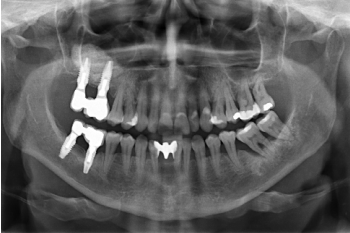

Transcurridos cuatro años, los molares del segundo y tercer cuadrante comienzan a tener una movilidad excesiva y problemas periodontales graves, por lo que se decide la extracción de los mismos y la regeneración de los alveolos con PRGF-Endoret. Una vez regenerada la zona (mes y medio después) se procede a la obtención de un Cone-beam para evaluar el volumen óseo residual. En el mismo se puede observar cómo existe una cresta ósea desigual con zonas de 3,3 mm de altura hasta 7 mm como máximo (Figuras 9 y 10). En esta ocasión, debido al cambio de protocolo descrito anteriormente, se opta por la inserción de implantes extra-cortos de forma directa, ya que los protocolos quirúrgicos para abordar este tipo de situaciones en el año 2011 variaron sustancialmente, siendo estos implantes una herramienta de primera línea para el tratamiento de este tipo de atrofias (Figura 11). Se seleccionan dos implantes extra-cortos (5,5 mm de diámetro x 6,5 mm de longitud para la pieza dental número 26 y 6 mm de diámetro por 5,5 mm de longitud para la pieza dental número 27).

Una vez transcurridos seis meses desde la inserción de los implantes extra-cortos, se procede a la colocación de la prótesis definitiva, en este caso, atornillada y con un componente intermedio (transepitelial), al igual que se confecciona del mismo modo la prótesis inferior del tercer cuadrante. En este punto cronológico, la filosofía de

trabajo mediante prótesis atornillada con transepitelial y la búsqueda de hermetismo y ajuste pasivo es la filosofía dominante para la rehabilitación sobre implantes y continúa siéndolo hoy en día (Figura 12).